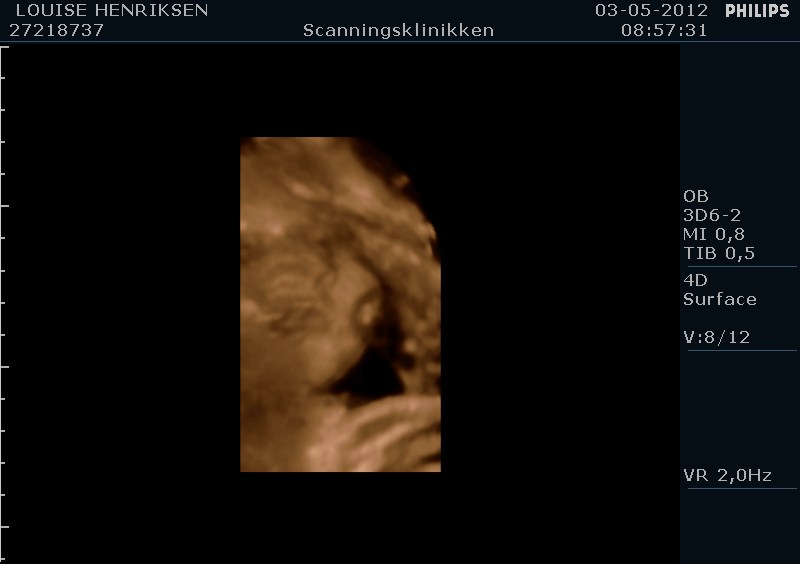

I dag skulle manden overraskes med en 4 d scanning.... og hans far var også med det var også en overraskelse, samt den lille prins....han fik bind for øjene og vi kørte mod scanning klinikken.... vi fik nogle gode sekvenser af bettemanden.. men han fylder en del derinde nu, så billederne blev ikke voldsomt gode.. men nogle fik vi dag...jeg skulle i morgen være 32 fulde uger.. mne scanningen i dag vidste34+4 dage yiarks.... jeg skal til at være færdig med den bachelor..... han vejede efter målene 1871 gram.....

så han var en fin basse...